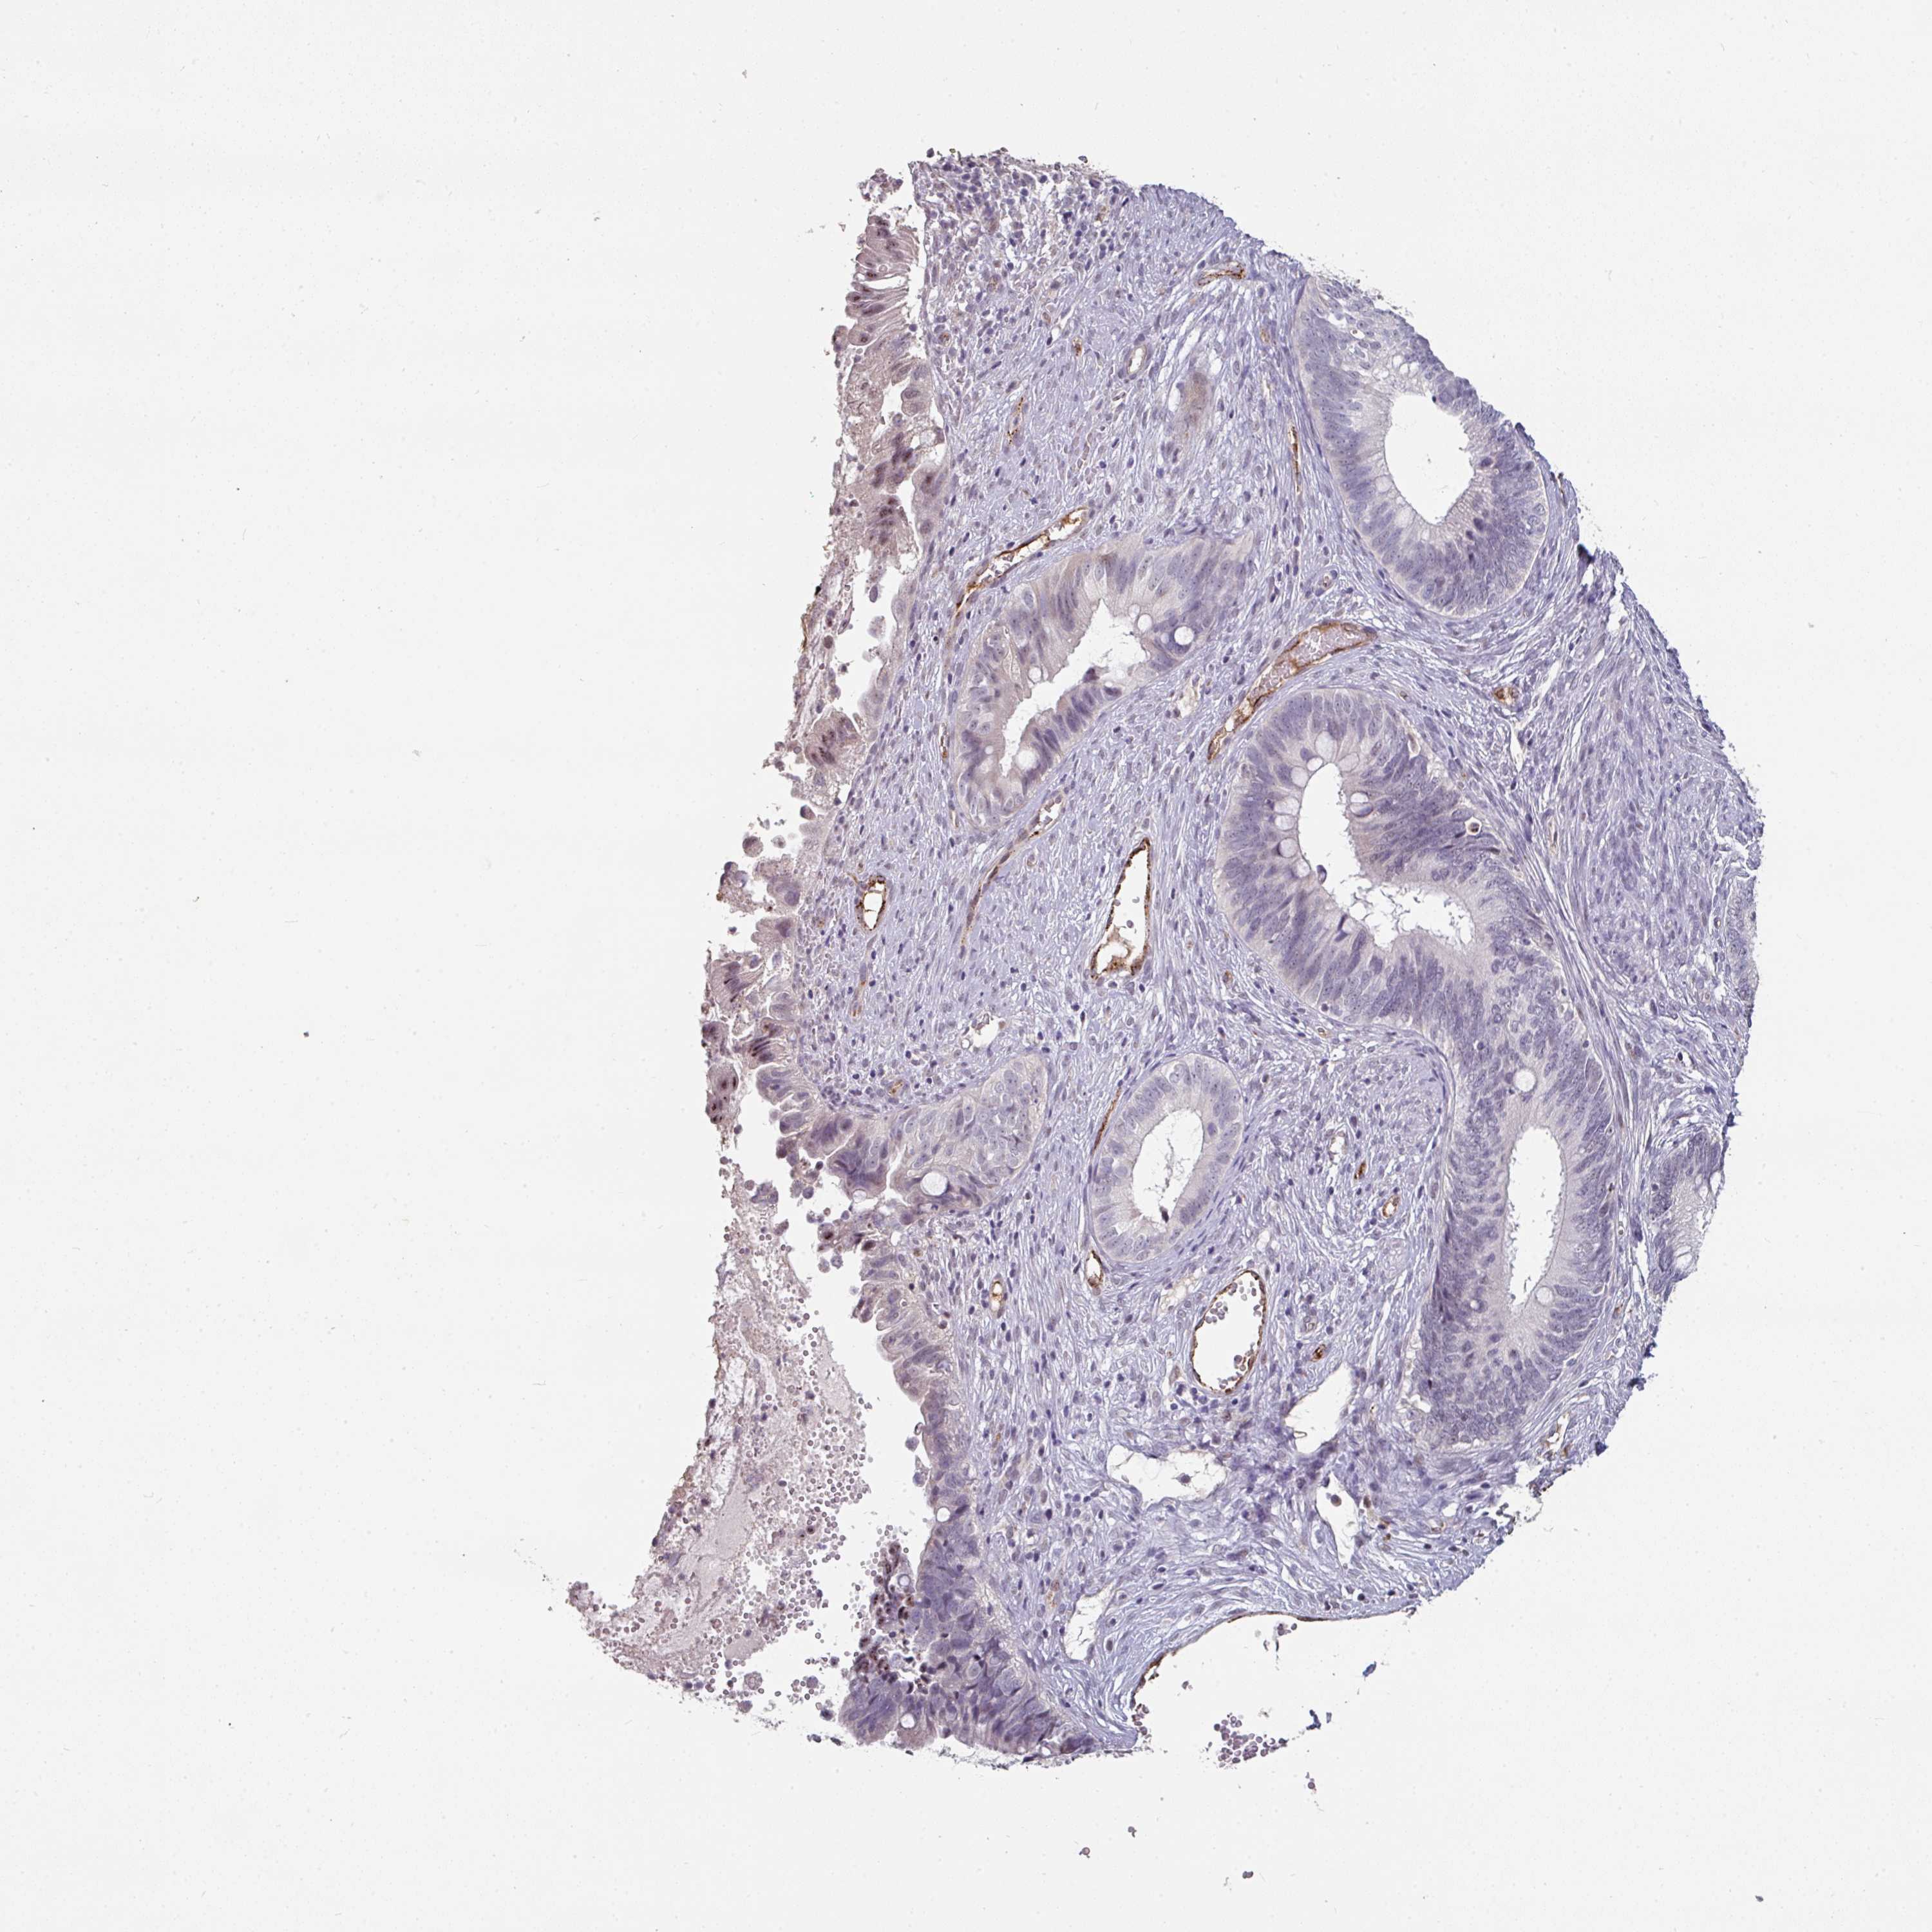

CERVICAL CANCER - Protein expressioni

A mouse-over function shows sample information and annotation data. Click on an image to view it in a full screen mode. Samples can be filtered based on level of antibody staining by selecting one or several of the following categories: high, medium, low and not detected. The assay and annotation is described here.

Note that samples used for immunohistochemistry by the Human Protein Atlas do not correspond to samples in the TCGA dataset.

Antibody stainingi

Antibody staining in the annotated cell types in the current human tissue is reported as not detected, low, medium, or high, based on conventional immunohistochemistry profiling in selected tissues. This score is based on the combination of the staining intensity and fraction of stained cells.

Each image is clickable and will lead to virtual microscopy that enables deeper exploration of all samples and also displays staining intensity scores, fraction scores and subcellular localization as well as patient and tissue information for each sample.

Antibody HPA052352

Staining

High

Medium

Low

Not detected

Intensity

Strong

Moderate

Weak

Negative

Quantity

>75%

75%-25%

<25%

None

Location

Nuclear

Cytoplasmic/membranous

Cytoplasmic/membranous,nuclear

Squamous cell carcinoma, NOS

Adenocarcinoma, NOS